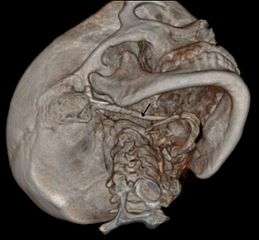

CT scan, coronal section showing bilateral extended styloid process and stylohyoid ligament ossification (incidental finding)

3D-reconstructed CT scan showing bilateral stylohyoid ligament ossification- 3D reconstructed CT scan showing elongated styloid process (right side)

Imaging is important and is diagnostic. Visualizing the styloid process on a CT scan with 3D reconstruction is the suggested imaging technique.[6] The enlarged styloid may be visible on an orthopantogram or a lateral soft tissue X ray of the neck.